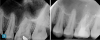

Figure 1 and Figure 2 provide examples of some cases that the author treated using the single-visit endo-restorative workflow. Despite the complex or challenging anatomy shown in these radiographs, the canals were able to be thoroughly irrigated by the multisonic irrigation system that was used with this workflow. For these cases, the one-day treatment workflow and the use of multisonic irrigation as described in this article enabled successful root canal treatment and improved patient satisfaction.

workflow). Fig 2, left panel: Preoperative radiograph of tooth No. 30 with internal inflammatory root resorption, a rare condition, resulting in acute periapical abscess in

another 20-year-old male patient with good dental and overall health. Fig 2, right panel: Postoperative radiograph (after the single-visit endo-restorative workflow).

Fig 2. Using the endo-restorative workflow described in this article, the complex anatomy shown in these radiographs was able to be irrigated by multisonic

Figure 2